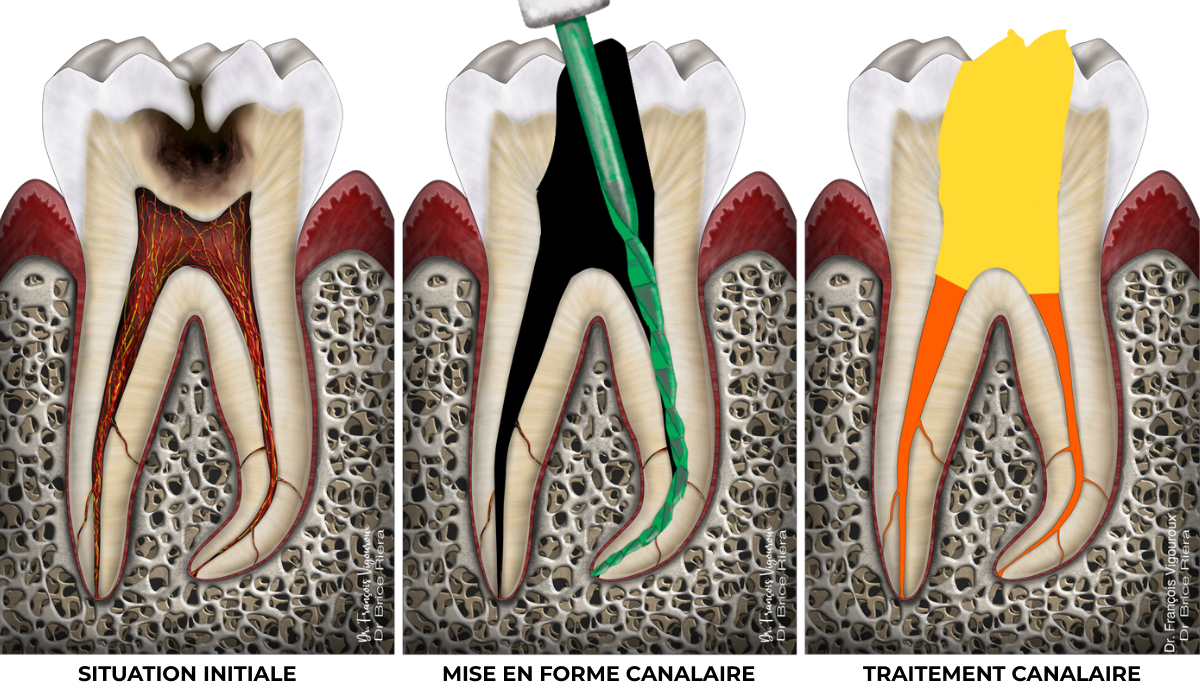

Traitement canalaire

Il existe 2 situations pour lesquelles le traitement canalaire peut être indiqué.

Soit la pulpe radiculaire ne peut pas être conservée vivante (coiffages et pulpotomies impossibles), généralement en raison d’une inflammation trop importante.

Soit la pulpe n’est plus vivante, elle est alors dite nécrosée.

Ce qui n’est plus vivant dans l’organisme s’infecte. D’où l’indication de réaliser le traitement de désinfection de l’intérieur de la dent (endodonte) : c’est le traitement canalaire.

Cette nécrose pulpaire peut, si l’endodonte est infecté, avoir causé une réaction inflammatoire osseuse, c’est la lésion apicale :

En l’absence de lésion apicale, le traitement canalaire a pour objectif de maintenir la bonne santé osseuse péri apicale.

En présence d’une lésion apicale, le traitement canalaire a pour objectif de permettre la cicatrisation osseuse péri apicale.

Cas clinique

Traitement canalaire : 80-95% de taux de succès